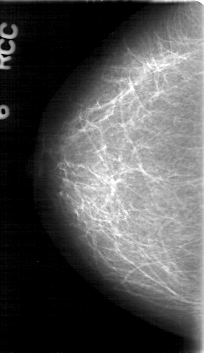

D_4083_1.RIGHT_CC

RIGHT_CC LINES 5281 PIXELS_PER_LINE 3046 BITS_PER_PIXEL 12 RESOLUTION 43.5 NON_OVERLAY